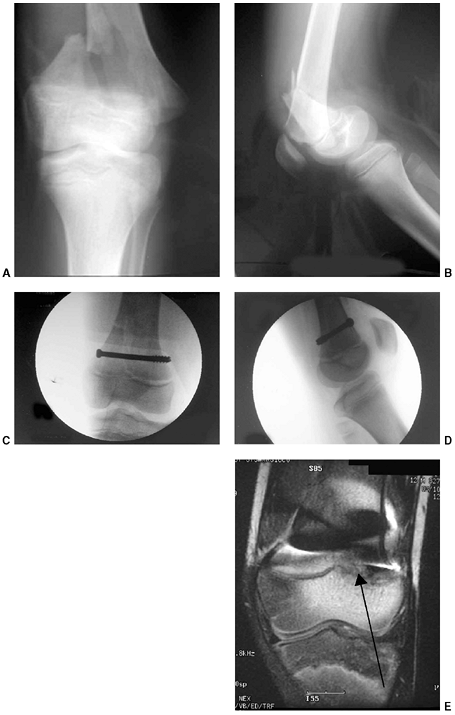

![]() |

Figure 33.3 Distal tibial growth arrest. A: Distal tibial physeal Salter-Harris type IV injury treated with cast immobilization without reduction. B:

Two years later, there is varus angulation to the distal tibia from a medial physeal bar. The Harris growth arrest line is not parallel to the distal physis, and does not extend across the entire width of the metaphysis. |